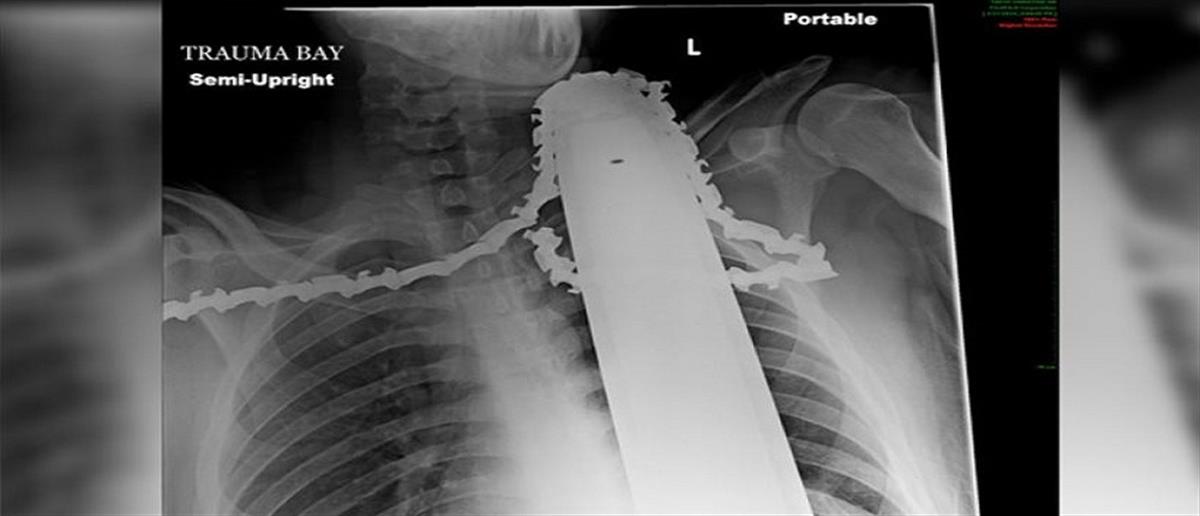

Αλυσοπρίονο καρφώθηκε στον λαιμό ξυλοκόπου!

Άγιο είχε ένας εργάτης 21 ετών όταν η λάμα αλυσοπρίονου καρφώθηκε στο λαιμό του τραυματίζοντας τον ευτυχώς όχι θανάσιμα.

Ο 21χρονος James Valentine εργαζόταν ως ξυλοκόπος στο Πίτσμπουργκ. όταν συνέβη το ατύχημα… Η λάμα από το αλυσοπρίονο που κρατούσε και δούλευε του καρφώθηκε κυριολεκτικά στο λαιμό.

Οι γιατροί που κλήθηκαν να αντιμετωπίσουν το περιστατικό τόνισαν πως ουδέποτε έχουν δει κάτι παρόμοιο ενώ δεν πίστευαν στα μάτια τους όταν διαπίστωσαν πως ο Valentine ήταν σε θέση να μιλά αφού δεν χτυπήθηκε ούτε η καρωτίδα του ούτε και ο οισοφάγος του.

Το περιστατικό αντιμετωπίστηκε επιτυχώς, ενώ αξιοσημείωτη ήταν και η ψυχραιμία του 21χρονου ο οποίος δεν πανικοβλήθηκε, καθώς θα μπορούσε να προσπαθήσει να τραβήξει τη λάμα μόνος του και να αιμορραγήσει ανεξέλεγκτα ή να πάθει ασφυξία..